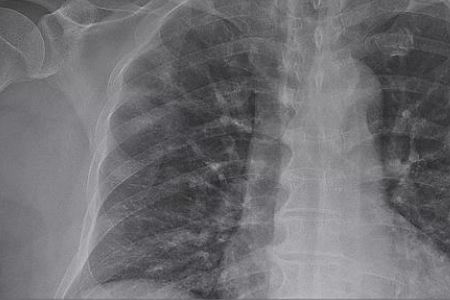

据美国有线新闻网(CNN)报道,官方消息称,美国已有125人感染新冠肺炎,死亡病例为9人。根据美国疾病控制和预防中心(CDC)的数据,其中48例是从日本“钻石公主”号和中国武汉的撤侨人员,其他77例分布在13个州。125个病例中包括确诊病例和在公共卫生实验室检测呈阳性的假定阳性病例,这些病例正在等待美国疾病控制与预防中心的确认。

另外,当地时间3月3日,美国纽约州州长科莫表示,一名居住在威彻斯特县并在曼哈顿工作的男子成为纽约州第二例确诊新冠病毒感染者,这也是首例“社区传播”病例。据了解该男子出现呼吸道症状,在周一入院测试,目前症状严重。科莫说,对该男子的旅行进行初步审查后并未发现其在疫情暴发时有任何去中国或其他国家的旅行记录,因此当局将其视为可能的社区传播,这也是美国第五例明显社区传播案例。(备注:信息来源“中国新闻网”。)